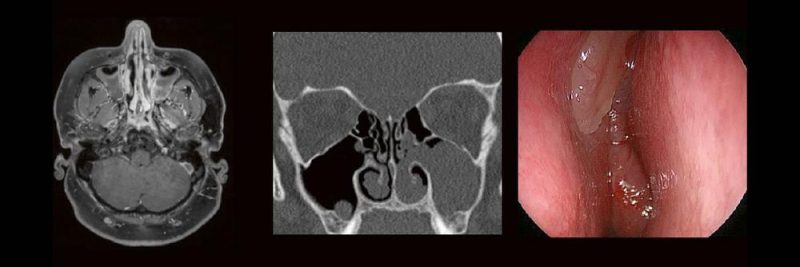

Die bildgebende HNO-Diagnostik macht es Anfängern nicht leicht. Die Anatomie ist komplex und weniger intuitiv als in anderen Körperregionen.

Normvarianten erschweren insbesondere in den Nasennebenhöhlen den Lernprozess. Sobald pathophysiologische Zusammenhänge verstanden und wichtige klinische Aspekte verinnerlicht wurden, gelingt es einen praxistauglichen, belastbaren Befund zu erstellen.

Gemeinsam mit einem HNO-Chirurgen werfen wir einen Blick IN die NNH – mal in grau, mal in Farbe. Denn alles fällt leichter, sobald man verstanden hat, warum man es tut.